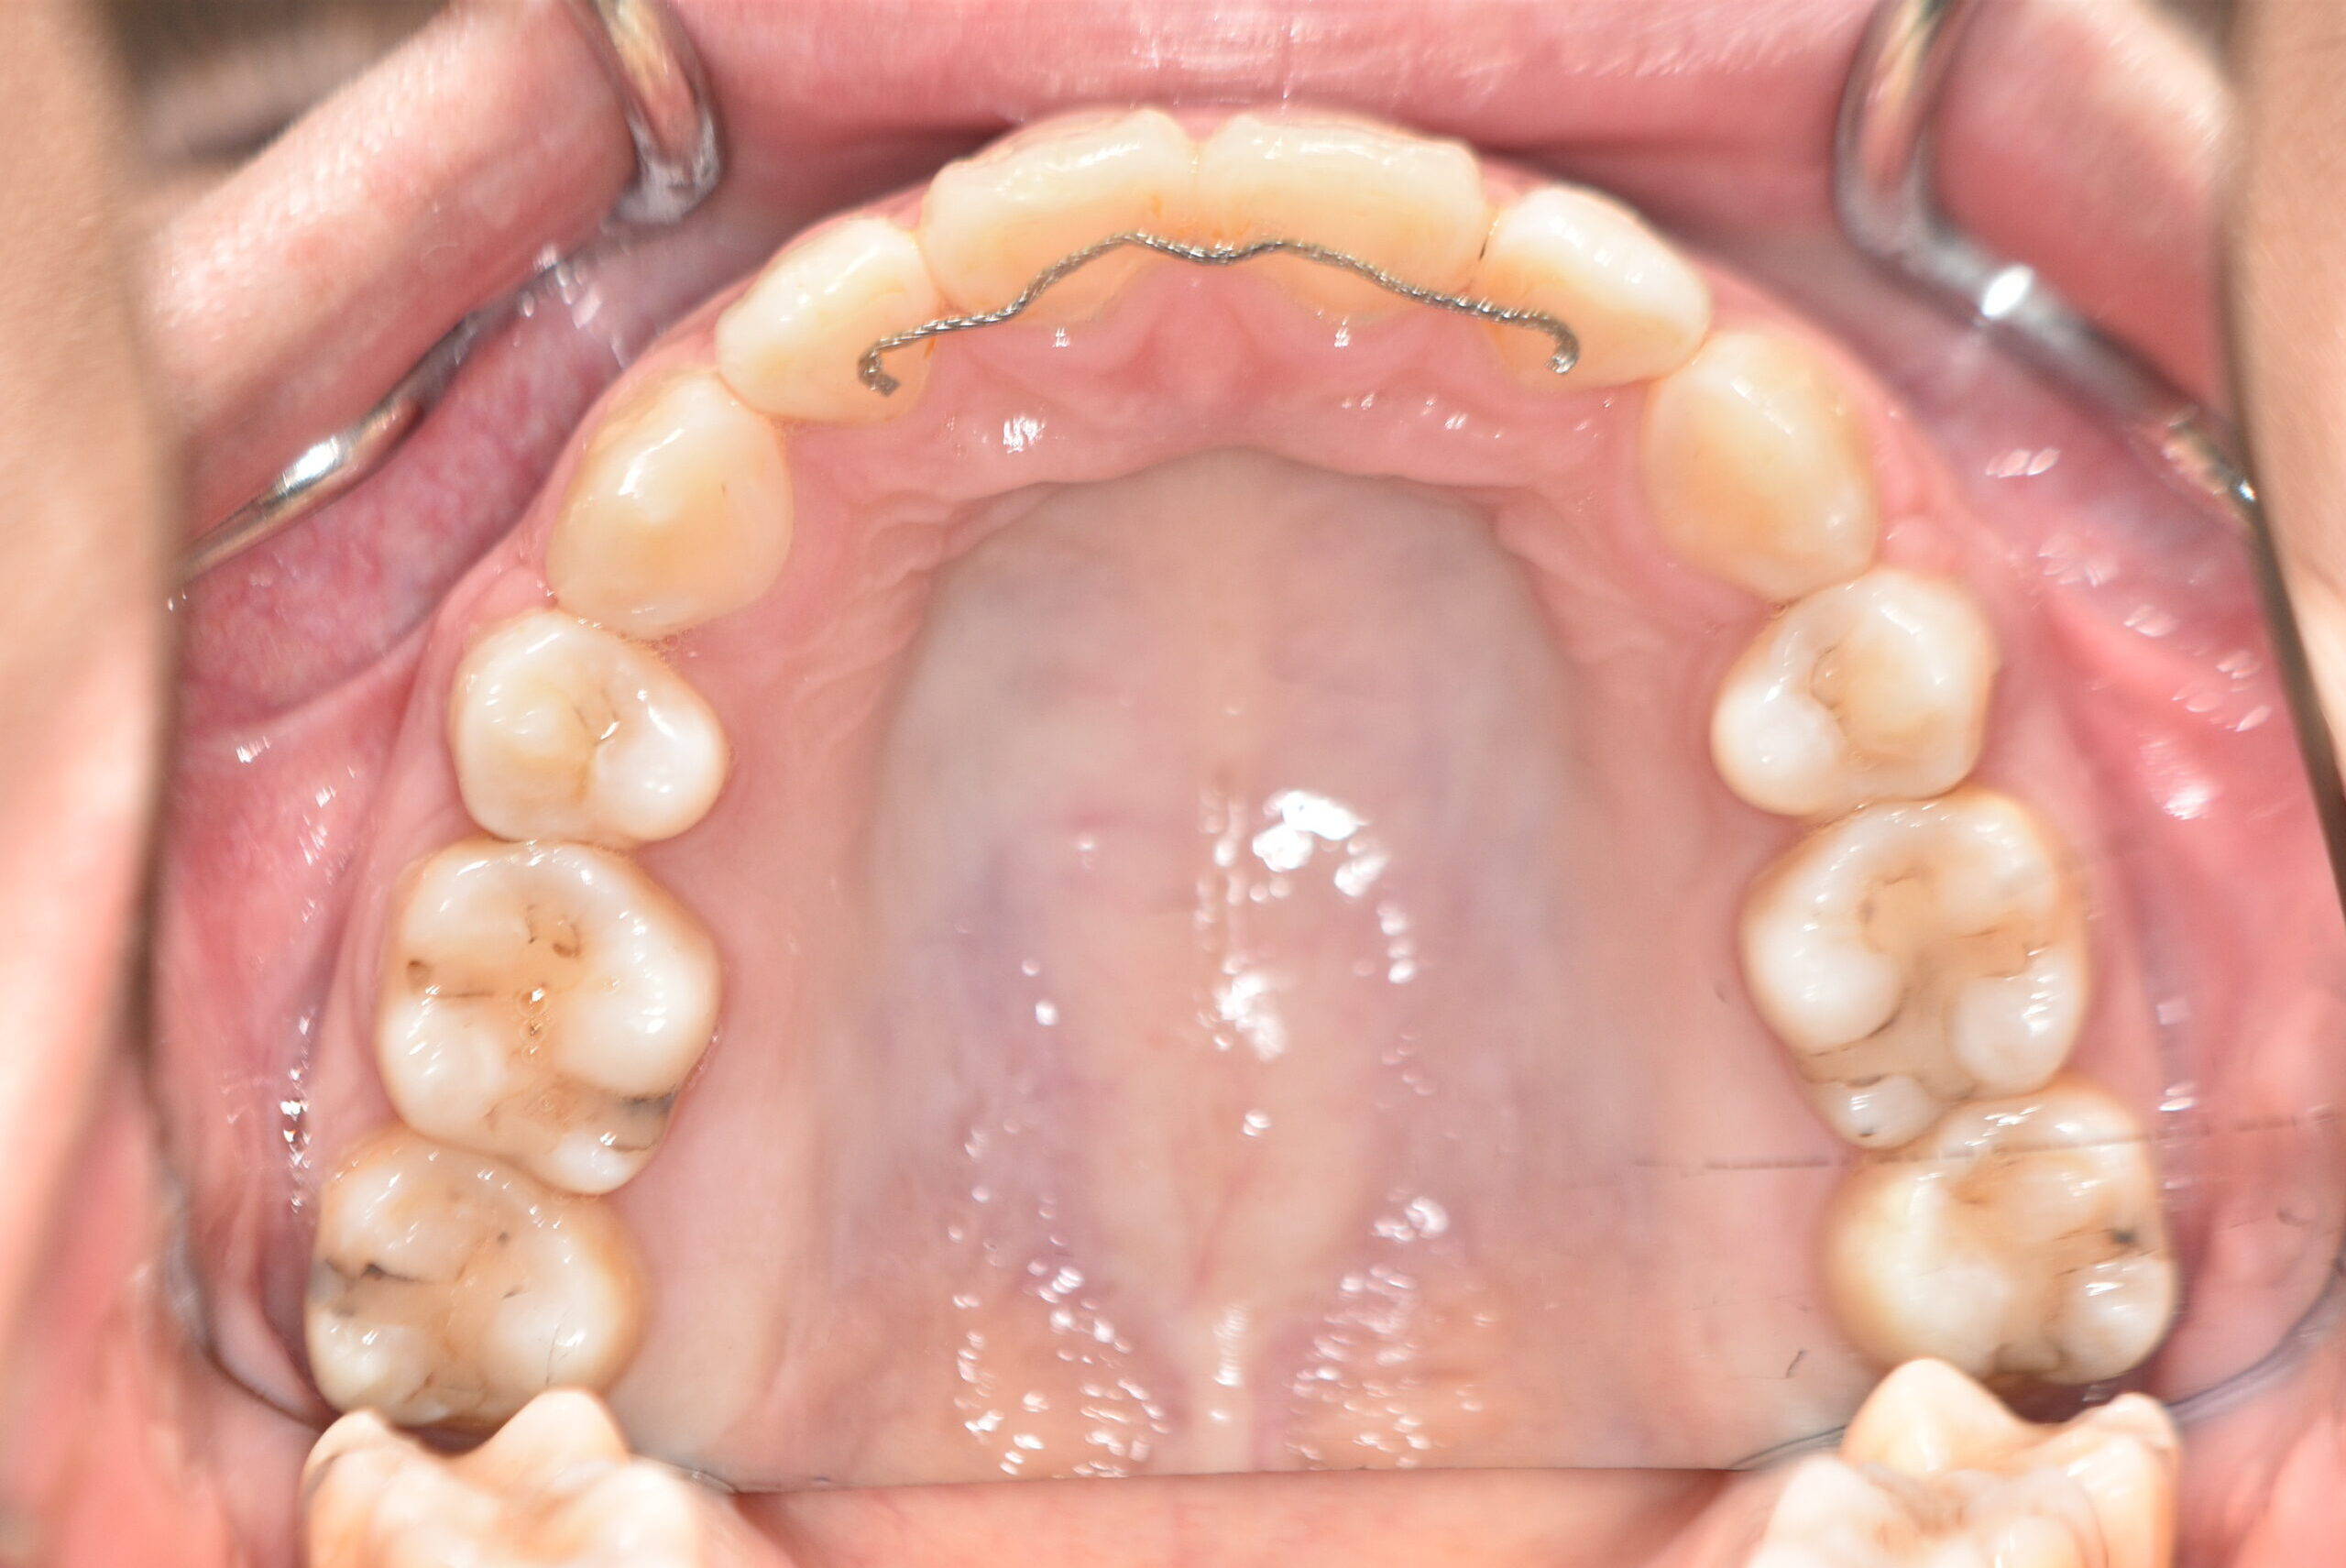

| 治療内容の詳細 | 初診時29歳の女性で、出っ歯を気にされ来院されました。 検査の結果、上顎前突を伴うアングルⅡ級1類不正咬合と診断しました。 治療としては、上顎左右第1小臼歯および下顎左右第2小臼歯をして、セルフライゲーションブラケット装置(デーモンシステム)で歯の配列を行いました。 同時に顎間ゴムにて咬合関係の改善を行いました。 この際、上顎に歯科矯正用アンカースクリューを設置し上顎前歯部後退時の土台としました。 治療期間は、2年6ヶ月でした。 |